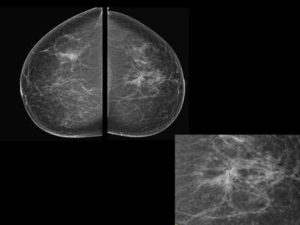

Mammography

52 year old lady with right breast mass of recent onset...

Read More